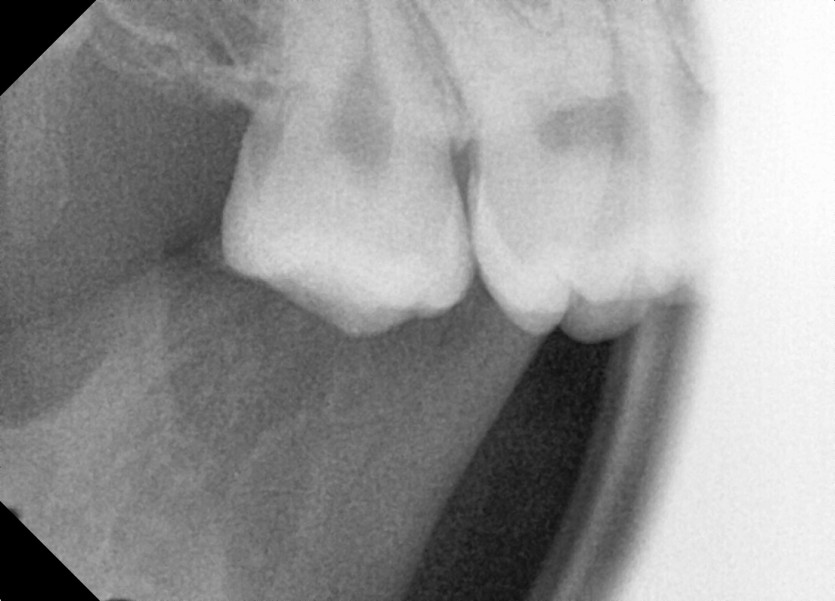

#18,48 사랑니 발치

구강외과 전문의가 당일 발치했습니다.